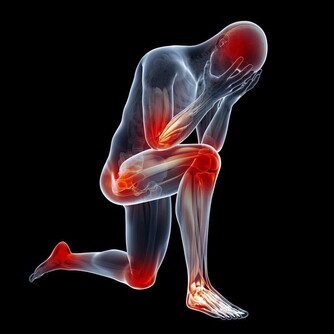

2、堅持運動

運動是幫助降尿酸的好技能,人體在運動的時候,能夠使體溫升高,排出大量汗液,體內的尿酸也會同排泄物一塊排出體外,降低體內尿酸的水平。